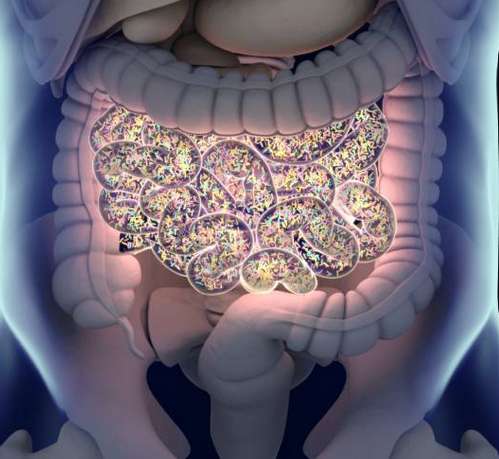

Syndrome de l’intestin irritable

Quand le ventre dicte le quotidien

Ballonnements, douleurs, inconfort digestif

Alimentation source d’anxiété

Peur de manger certains aliments

Impact sur la vie sociale et émotionnelle